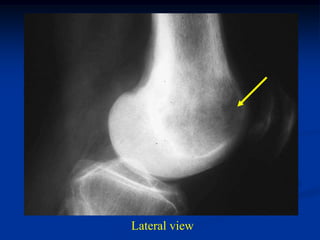

Case #1143             Metastatic Lung

73 year male with lytic lung met to the intercondylar area

Lateral view